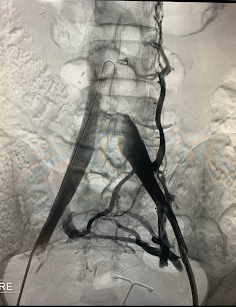

• Deep Venous Reconstruction (Iliofemoral and Post-Thrombotic Disease) Specialized management of iliofemoral obstruction, post-thrombotic disease, and complex venous outflow compromise, with the goal of restoring venous return and improving functional outcomes. Guided by reconstruction of venous outflow and optimization of global hemodynamics based on individual flow patterns.

Comprehensive training in open and endovascular surgery, with a particular focus on deep venous reconstruction, iliofemoral obstruction, and post-thrombotic disease — areas that currently define a core component of my specialized clinical practice.